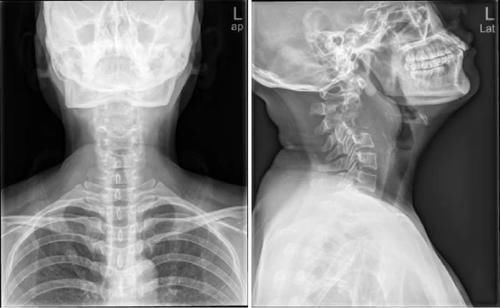

Case12:F,4y;患儿颈部活动受限1个月。

文章插图